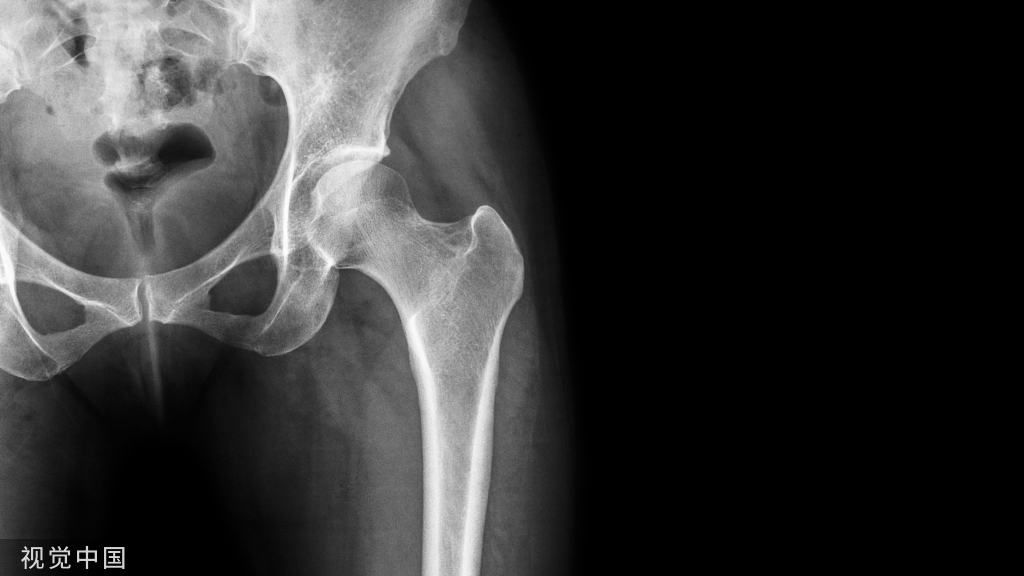

骨质疏松症是全身骨骼成分减少的一种现象,就是破骨细胞把骨头吃掉了,主要表现为骨组织内单位体积中骨量减少,由于骨质疏松症病程缓慢而常被忽略,直到发生骨折,被称为寂静的杀手